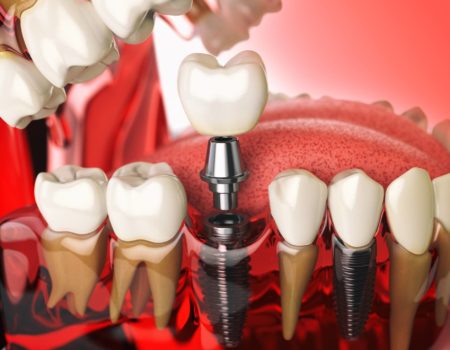

Los implantes dentales son una forma popular y muy efectiva de reemplazar los dientes perdidos,están diseñados para tener una gran estética y disimularse entre los otros dientes. Son una excelente opción a largo plazo para restaurar su sonrisa. En ANGLODENT encontraras a los mejores implantologos que haran de tu sonrisa algo excepcional.